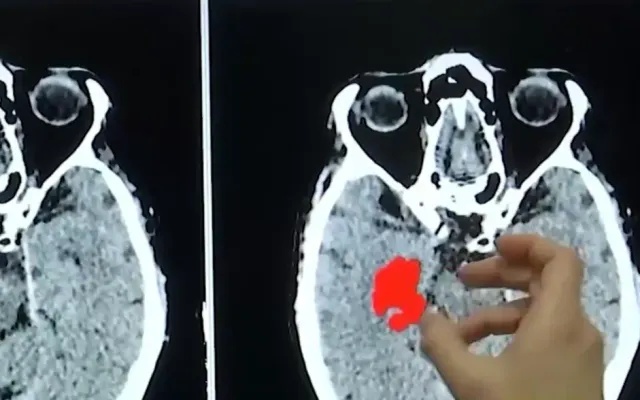

2. Suýt mất mạng sau khi uống thuốc tiểu đường chứa chất cấm

Ngày 26/4, đại diện Bệnh viện 71 Trung ương cho biết bệnh nhân được chuyển vào Khoa Hồi sức tích cực trong tình trạng nguy kịch do suy thận cấp, rối loạn điện giải. Bà bị bệnh đái tháo đường nhiều năm nhưng không điều trị theo phác đồ của bác sĩ. Thay vào đó, bệnh nhân dùng thuốc nam và một số loại thuốc dạng viên do người quen giới thiệu mua trên mạng.

4. Nữ bệnh nhân nguy kịch sau uống thuốc mua trên mạng

Nữ bệnh nhân phải cấp cứu trong tình trạng nguy kịch, suy thận cấp vì trước đó đã mua thuốc chữa tiểu đường dạng viên do người quen giới thiệu trên mạng về uống.